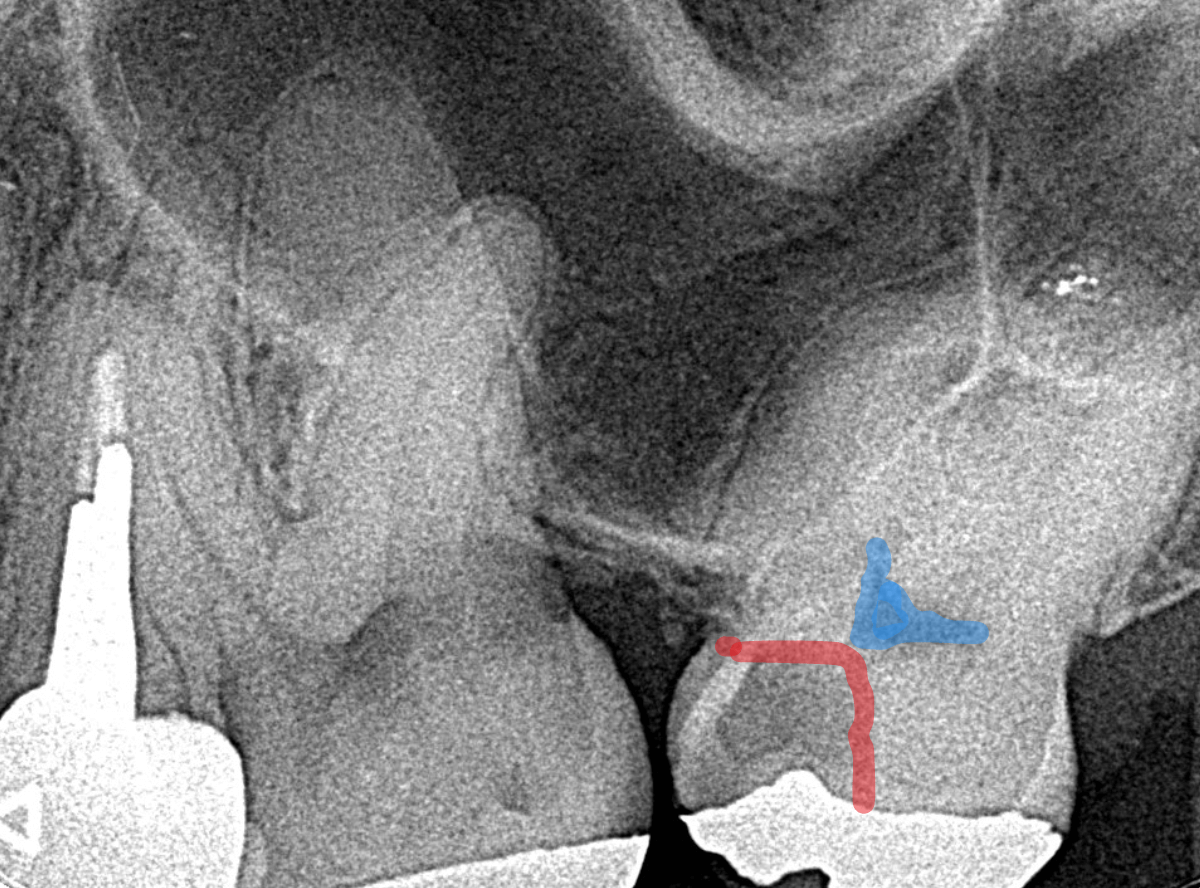

Case.14 インレーの下の歯肉まで広がった虫歯

「下の奥歯が噛むと痛む」という症状で来院された患者さんのケースです。

お口の中の状態を確認すると、奥歯の端に穴が開いているのが見えます。

ここかな?

レントゲン写真で確認します。

やはり、奥歯の端が大きな虫歯になっています。

青いラインが歯の神経、赤いラインが虫歯です。

レントゲン写真上では虫歯が神経まで達しているように見えます。

これは、神経を取らないとダメかもしれません。